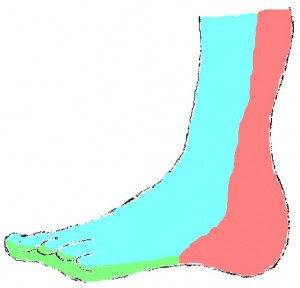

The foot consists of 6 angiosomes in total (Figure 1):

- The posterior tibial supplies 3 angiosomes through the medial calcaneal, medial plantar, and lateral plantar braches (medial ankle and plantar surface).

- The anterior tibial artery supplies the dosalis pedis angiosome encompassing the entire dorsal aspect of the foot.

- The peroneal artery supplies 2 angiosomes through the lateral calcaneal and anterior perforating branches (lateral heel and anterolateral ankle).